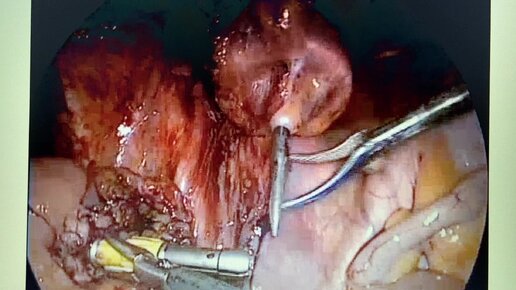

Аппаратный толстокишечный шов